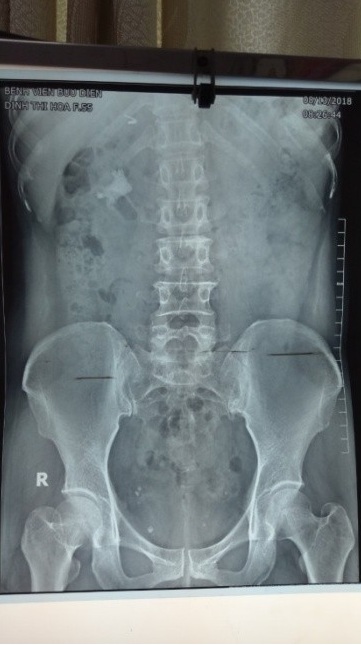

Trước tán sỏi

Sỏi được tán

Sau tán sỏi